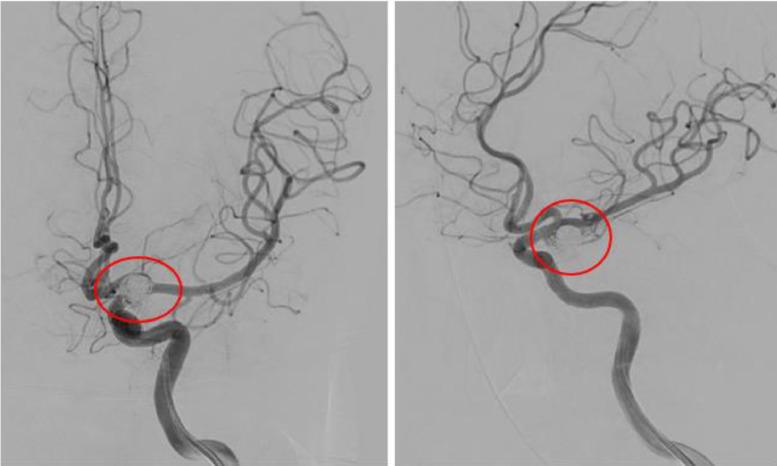

Patients with an acute subdural hematoma (aSDH) usually have a history of head trauma, but some patients may present with spontaneous aSDH due to a ruptured aneurysm. Spontaneous aSDH is a rare manifestation of aneurysmal rupture. However, aneurysmal rupture remains a major cause of spontaneous aSDH. A 42-year-old man was brought to the emergency room because of a sudden loss of consciousness during sexual intercourse. The patient has seizures and weakness on the right side of his body. The patient has no history of trauma and has never taken anticoagulant or antiplatelet drugs, sexual aphrodisiacs, or other drugs. Physical examination revealed the Glasgow Coma Scale of E2V1M3, ptosis on the left eye, left pupil mydriasis, right central facial palsy, and right hemiparesis. Laboratory results showed hypercoagulopathy. Noncontrast head computed tomography scan revealed subdural hematoma with no subarachnoid or intraparenchymal hemorrhage. The patient underwent an emergency craniotomy, and the hematoma was evacuated. Cerebral angiography was performed 1 week later, revealing a saccular aneurysm in the left posterior communicating artery. The patient has successfully undergone endovascular coiling and was discharged from the hospital in good condition, fully conscious, with no weakness in half side of the body, but there is still third nerve palsy. Patients with pure aSDH without a history of trauma should consider the possibility of aneurysm rupture and perform an angiographic examination to rule out vascular malformations so that the patient can receive appropriate treatment.

急性硬膜下血肿(aSDH)患者通常有头部外伤史,但部分患者可能因动脉瘤破裂出现自发性aSDH。自发性aSDH是动脉瘤破裂的罕见表现。然而,动脉瘤破裂仍是自发性aSDH的主要原因。一名42岁男性因性交过程中突然意识丧失被送往急诊室。患者有癫痫发作及右侧身体无力症状。患者无外伤史,从未服用过抗凝药、抗血小板药物、性壮阳药或其他药物。体格检查显示格拉斯哥昏迷量表评分为E2V1M3,左眼上睑下垂,左侧瞳孔散大,右侧中枢性面瘫及右侧偏瘫。实验室检查结果显示高凝状态。头颅非增强计算机断层扫描显示硬膜下血肿,无蛛网膜下腔或脑实质内出血。患者接受了急诊开颅手术,血肿被清除。1周后进行脑血管造影,显示左侧后交通动脉有一个囊状动脉瘤。患者成功接受了血管内栓塞治疗,出院时情况良好,意识完全清醒,半身无无力症状,但仍有动眼神经麻痹。无外伤史的单纯aSDH患者应考虑动脉瘤破裂的可能性,并进行血管造影检查以排除血管畸形,以便患者能接受适当治疗。